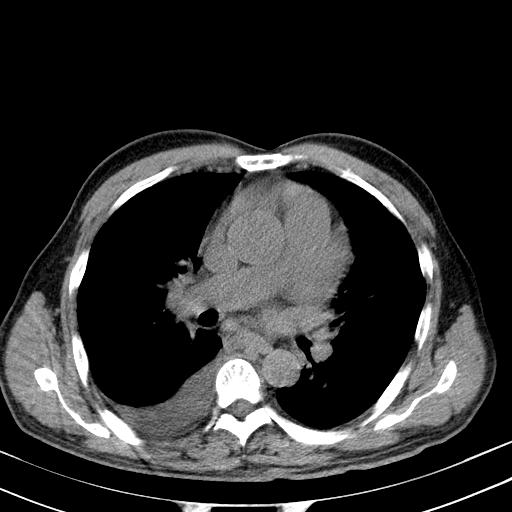

以下是引用zjzjr在2010-3-21 17:39:00的发言:[br]右下中心型肺癌并阻塞性肺炎/不张,纵膈淋巴结肿大,右侧大量胸腔积液,左侧少量胸腔积液

以下是引用zxl51642在2010-3-21 17:06:00的发言:[br]右下中心型肺癌并阻塞性肺炎/不张,纵膈淋巴结肿大,右侧大量胸腔积液,左侧少量胸腔积液,少量腹水。建议纤维支气管镜进一步检查。